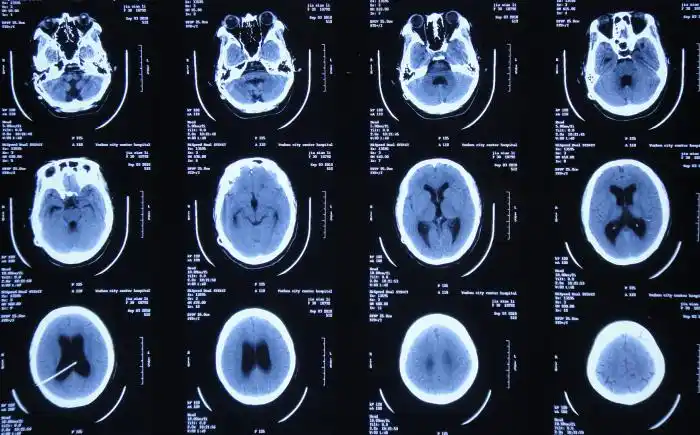

最全的颅脑常见病ct表现在这里!

颅脑ct的正常解剖

轴位平扫ct显示鞍上区肿物伴钙化,与颅咽管瘤表现一致.